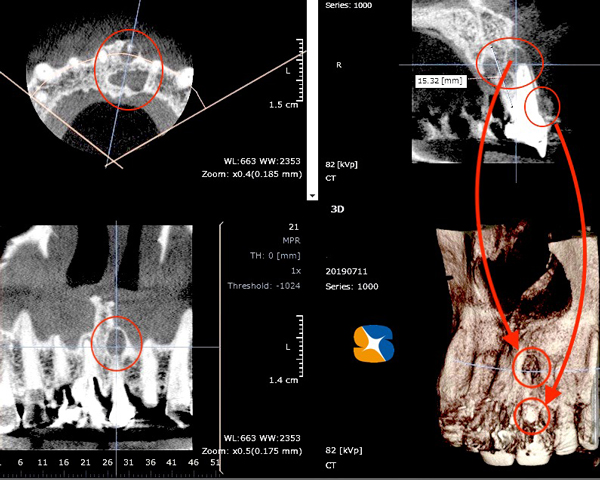

その後、CTで骨の状態を確認したうえで、以下のインプラント移植手を9月に行いました。

〈骨の厚み増加に成功〉

①側面から観たCT画像断面

②正面から観たCT画像断面

③頭上から観たCT断層写真

側面から観たCT画像断面

正面から観たCT画像断面

頭上から観たCT断層写真